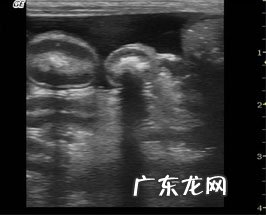

超声心动查验

超声心动查验:全部心腔均比较严重扩大 , 收缩期左心房內径LVDS 57.毫米(14.9~25.毫米) , 显著扩大 , 及其减少成绩FS=25%(33~46%)和射血分数EF减少 , EPSS扩大 , 提醒心房收拢作用较弱 。室中隔和左心房分散壁薄厚减少 。左心房LA/AO=3.64 , 提醒左心比较严重扩大 , 心力衰竭产生 。多谱勒精确测量二尖瓣返流 , 则继发性于心房比较严重扩大后 。